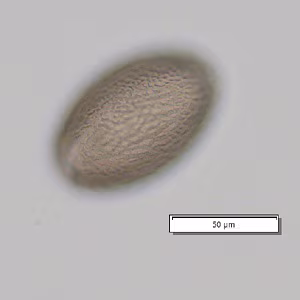

A 3-year-old boy was seen by a pediatrician for gastrointestinal pain and watery diarrhea. His parents conveyed that he has a propensity for putting insects in his mouth and sometimes eating them. A stool specimen was collected and processed for ova and parasites (O&P). A formalin-ethyl acetate (FEA) concentration was performed and a wet mount smear was prepared from the sediment and examined. Figures A and B show one parasite-like object at different focal planes at 200x magnification; another object from the sample is shown in Figures C and D, also at different focal planes, at 200x magnification. What is your diagnosis? Based on what criteria?

Figure A